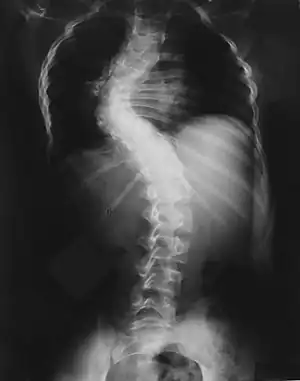

Pode causar lesões císticas nos ossos, geralmente danificando os metacarpos, falanges, ossos do quadril, fêmur e coluna vertebral. Quando causa compressão medular pode resultar em paraplegia [3] Foi descrita por von Recklinghausen em 1882.